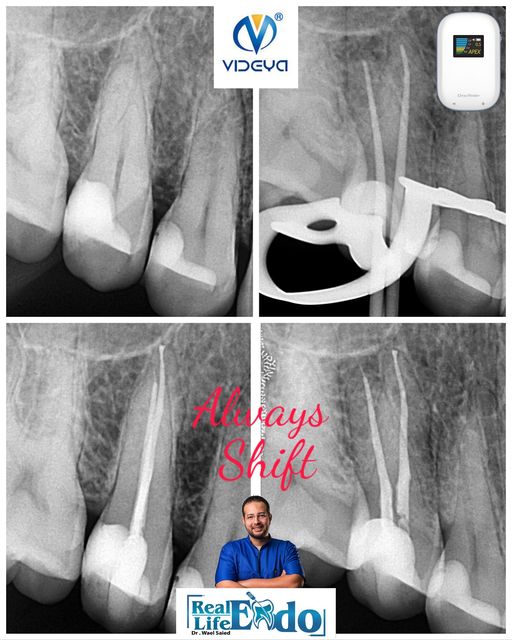

A Routine Endodontic Treatment For First Upper Molar With Acute Pulpitis